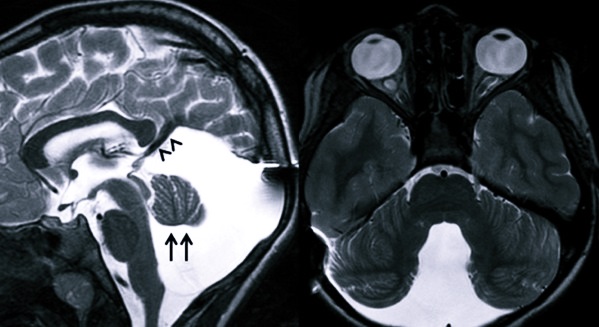

Подобная болезнь в развитии малыша определяется, когда проводится УЗИ уже вначале беременности. А именно, вся симптоматика этого недуга видна уже к 20-й неделе. Основное доказательство появления патологии – это всевозможные показатели, свидетельствующие о поражении в головном мозге: ясно видно кистозное формирование в ямке черепной коробки, плохо развивается мозжечок, чрезмерно расширен 4-й желудочек. Причем УЗИ-показатели ярче выражаются по мере того, как развивается плод.

Изначально можно заметить формирование такой симптоматики:

- Атрезии (зарастания либо природного недостатка) отверстия Мажанди и Лушки;

- Расширение в объемах задней ямки черепа;

- Отмирания мозжечковых полушарий;

- Появление кистозного формирования и свища;

- Гидроцефалии на разных стадиях.

- Делается КТ и МРТ. Во время процедуры определяют факт разрастания задней ямки черепной коробки, увеличения в объемах 4-го желудочка, скопления жидкости в мозговых пустотах, недоразвитие мозжечка.